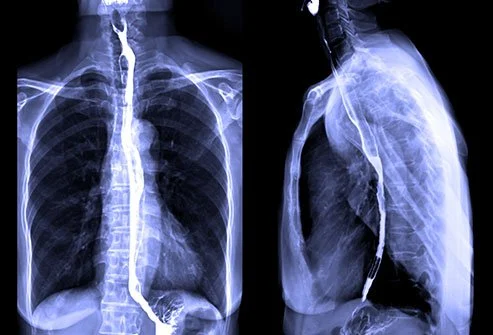

x-ray barium swallow upper gastrointestinal

A barium swallow, also known as an esophagogram, employs a specialized form of X-rays to see the upper digestive tract. The test entails ingesting a barium liquid that enhances the visibility of body parts. If you have difficulty swallowing, bloating, vomiting, and abdominal pain, the test can be conducted.